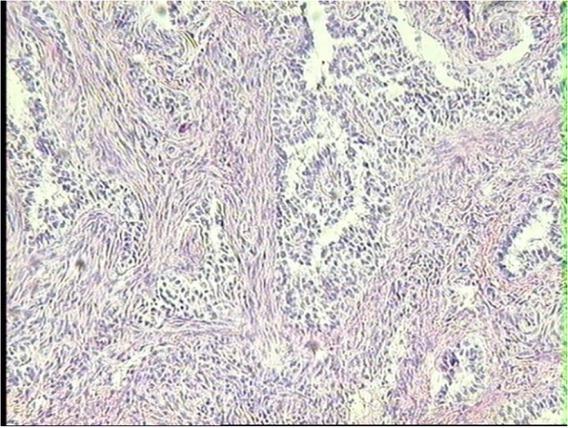

The tumour cell structure had characteristic focal blood vessel proliferation. In the periphery of the blood vessels, the walls were cuffed with neoplastic epithelioid cells (Fig. 4). In less advanced tumour tissue growth, the proliferation was mainly localised in the ovarian hilus. In cases with more advanced tumour proliferation, PEComa tissue reached the ovarian cortex border, but never grew beyond the ovarian capsule (Figs 5 and 6). There was some relation observed between the stages of the tumour tissue proliferation and the structure of PEComa neoplastic cells. In advanced tumour tissue growth, the neoplastic cells were smaller, with condensed hyperchromatic nuclei (Fig. 7), which may indicate the progress in their anaplastic changes.

Neoplastic PEComa tissue infiltrating ovarian stroma in the ovary of a dairy cow with an adenomyotic uterus. HE, 10×